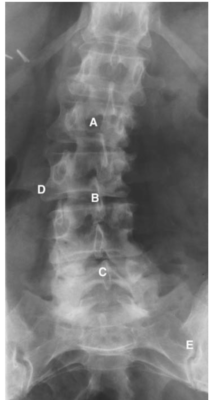

Cột sống thắt lưng

Các chữ viết tắt:

- A = L2 vertebral body; thân đốt sống L2

- B = L3/4 disc space; khoảng đĩa đệm L3/4

- C = Spinous process; mỏm gai

- D = Transverse process; mỏm ngang

- DG = Dorsal root ganglion of L2 in intervertebral foramen

- E = Sacroiliac (S–I) joint; Khớp cùng -chậu

- ES = Erector spinae muscle; cơ dựng gai

- F = Articular facet; Diện khớp nhỏ

- ID = Intervertebral disc; đĩa đệm

- L = Lamina of vertebral arch; bản cung

- L5 = L5 vertebral body; thân đốt L5

- N = Nerve root; Rễ thần kinh

- PI = Pars interarticularis; Phần liên mỏm khớp (eo)

- PL = Pedicle; cuống cung

- S = Spinal canal, cauda equina (C); ống tuỷ, đuôi ngựa

- SI = Sacroiliac joint; Khớp cùng chậu

- V =Vertebral body; Thân đốt sống